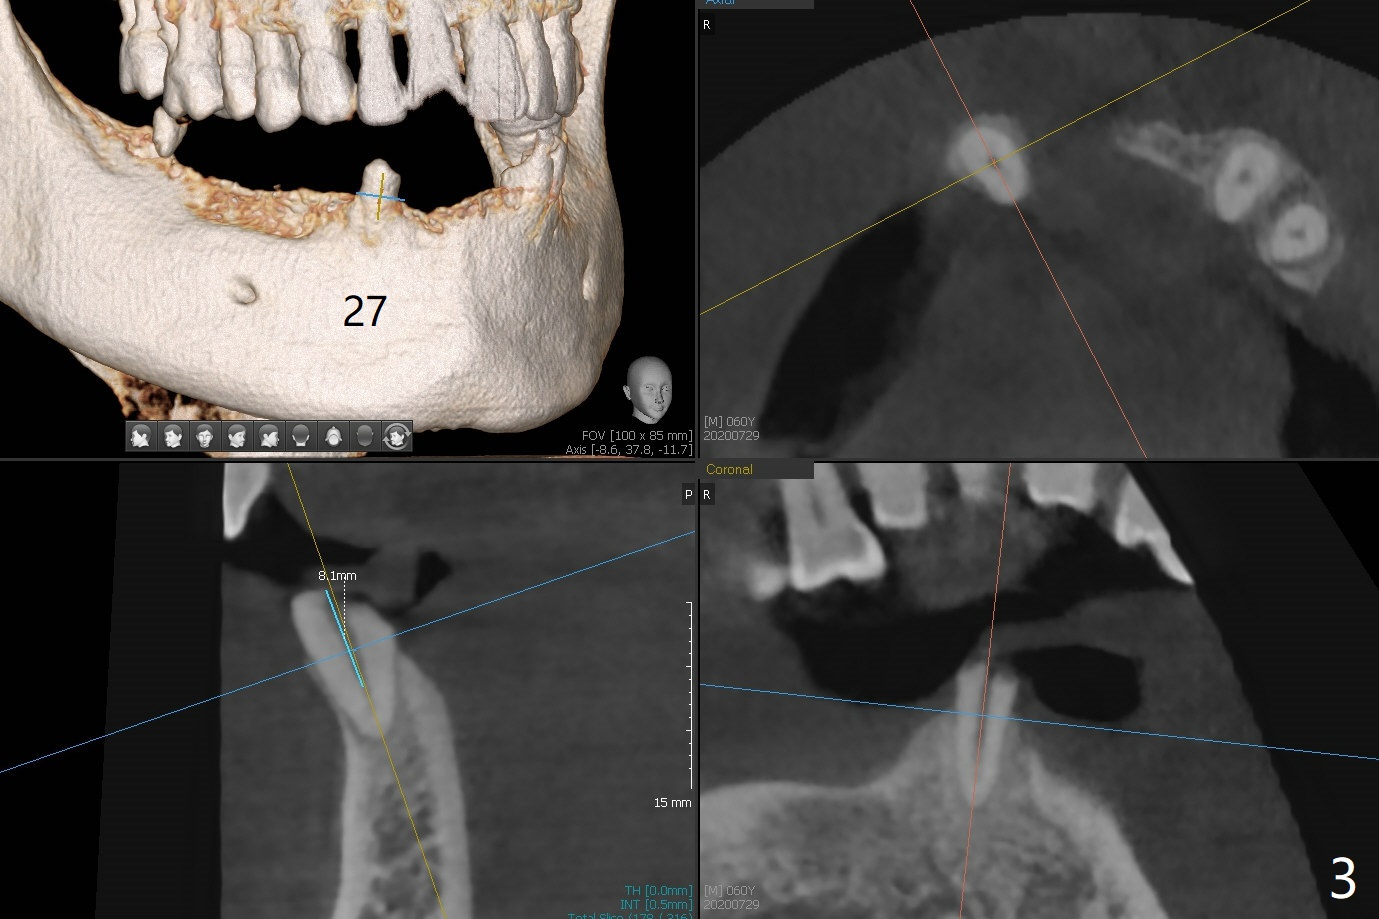

60岁男两年前回国制作下颌活动假牙,之后没有什么护理,五个基牙四个坏的厉害(图一(上面):21,22,27,31),初步计划:21,22,27号牙根管治疗(图二,三),31号牙拔除种植(申请保险,图四),都装上球状基台(ball abutment),增加托牙稳定性。当牙根基牙不行时,再逐步改做植牙。深洗和14号牙(图一)拔出后十四天病人回来进行27号牙(右下3)根管治疗(图五,六),工作长度13毫米,合适打桩做牙冠吗(原有局部托牙有卡环(Clasp and rest)?还是安置球冒更恰当?